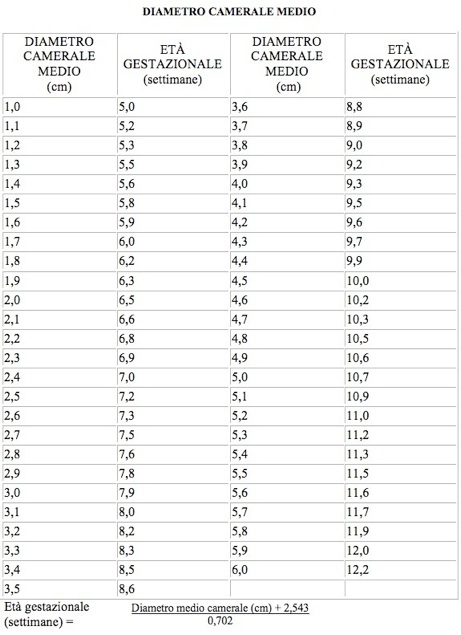

Tabelle crescita fetale CRL BPD CC CM CA FL feto sales, Feto a 5 settimane immagini e fotografie stock ad alta risoluzione Alamy sales, Tabelle fetali sales, Image of feto in posizione parto podalica con piede e mano caduto sales, Lunghezza piede bambino e numero scarpa Nostrofiglio sales, 16 settimana di gravidanza ecografia lunghezza e peso del feto sales, Piedi in gravidanza attenzione all alluce valgo Alluce valgo innovazione nell operazione chirurgica intervento mini invasivo sales, 20 settimana di gravidanza sintomi e sviluppo del bambino sales, Med 2000 eco sales, Feto del modello Baby Bambino strati Kind stellungen urologie modello a grandezza naturale Amazon Commercio Industria e Scienza sales, Trentesima Settimana Di Gravidanza Settimana 30 sales, La gravidanza mese per mese sviluppo fetale e cambiamenti nella madre sales, Ecografia Morfologica Dr Annona sales, PIEDE TORTO ilpiedetorto sales, Modello Anatomico Dell organo Neonatale Dei Neonati Del Cordone Ombelico Addominale Del Feto Placentale Modello Anatomico Per L insegnamento Della Classe studenti Modelli Medici E Materiali Educativi ... sales, Sviluppo del feto sales, Lo Sviluppo dell Embrione Feto sales, Omessa diagnosi di spina bifida del feto sales, Le Fasi della Gravidanza con la Frutta Donkid sales, Feto a 15 settimane immagini e fotografie stock ad alta risoluzione Alamy sales, Tabelle crescita fetale CRL BPD CC CM CA FL feto sales, 32 settimane di gravidanza peso feto e quanto manca al parto sales, PIEDE TORTO ilpiedetorto sales, 4.036 Feto High Res Illustrations Getty Images Gravidanza Neonato Embrione sales, Immagine prenatale 5D a 31 33 settimane di gravidanza emoxione sales, Modello di Feto per Bambini di 9 Mesi Bacino Femminile di Gravidanza con Organi Rimovibili Anatomia della Sezione Pelvica della Gravidanza Umana Modello Didattico Anatomico Amazon Commercio Industr... sales, Trentaduesima settimana di gravidanza Pampers sales, Trentottesima Settimana Di Gravidanza Settimana 38 sales, Tabelle fetali sales, Niente cesareo per non rimanere oltre il turno sales, Pressioni sull addome della partoriente e lesioni al feto sales, PIEDE TORTO ilpiedetorto sales, Tappetino di misurazione per misuratore di lunghezza del corpo del bambino neonato righello di crescita del bambino misura del corpo infantile AliExpress sales, Radiografia radioterapia e radioterapia FLG. 111. mostrando le ossa alla caviglia e al piede con epifisi edate a cui si uniscono con le diafisie. Interamente composto dall epifisi inferiore del fibula... sales, Oligoidramnios cause sintomi diagnosi terapie conseguenze rischi per il feto e la madre MEDICINA ONLINE sales.

Tabelle crescita fetale CRL BPD CC CM CA FL feto sales, Feto a 5 settimane immagini e fotografie stock ad alta risoluzione Alamy sales, Tabelle fetali sales, Image of feto in posizione parto podalica con piede e mano caduto sales, Lunghezza piede bambino e numero scarpa Nostrofiglio sales, 16 settimana di gravidanza ecografia lunghezza e peso del feto sales, Piedi in gravidanza attenzione all alluce valgo Alluce valgo innovazione nell operazione chirurgica intervento mini invasivo sales, 20 settimana di gravidanza sintomi e sviluppo del bambino sales, Med 2000 eco sales, Feto del modello Baby Bambino strati Kind stellungen urologie modello a grandezza naturale Amazon Commercio Industria e Scienza sales, Trentesima Settimana Di Gravidanza Settimana 30 sales, La gravidanza mese per mese sviluppo fetale e cambiamenti nella madre sales, Ecografia Morfologica Dr Annona sales, PIEDE TORTO ilpiedetorto sales, Modello Anatomico Dell organo Neonatale Dei Neonati Del Cordone Ombelico Addominale Del Feto Placentale Modello Anatomico Per L insegnamento Della Classe studenti Modelli Medici E Materiali Educativi ... sales, Sviluppo del feto sales, Lo Sviluppo dell Embrione Feto sales, Omessa diagnosi di spina bifida del feto sales, Le Fasi della Gravidanza con la Frutta Donkid sales, Feto a 15 settimane immagini e fotografie stock ad alta risoluzione Alamy sales, Tabelle crescita fetale CRL BPD CC CM CA FL feto sales, 32 settimane di gravidanza peso feto e quanto manca al parto sales, PIEDE TORTO ilpiedetorto sales, 4.036 Feto High Res Illustrations Getty Images Gravidanza Neonato Embrione sales, Immagine prenatale 5D a 31 33 settimane di gravidanza emoxione sales, Modello di Feto per Bambini di 9 Mesi Bacino Femminile di Gravidanza con Organi Rimovibili Anatomia della Sezione Pelvica della Gravidanza Umana Modello Didattico Anatomico Amazon Commercio Industr... sales, Trentaduesima settimana di gravidanza Pampers sales, Trentottesima Settimana Di Gravidanza Settimana 38 sales, Tabelle fetali sales, Niente cesareo per non rimanere oltre il turno sales, Pressioni sull addome della partoriente e lesioni al feto sales, PIEDE TORTO ilpiedetorto sales, Tappetino di misurazione per misuratore di lunghezza del corpo del bambino neonato righello di crescita del bambino misura del corpo infantile AliExpress sales, Radiografia radioterapia e radioterapia FLG. 111. mostrando le ossa alla caviglia e al piede con epifisi edate a cui si uniscono con le diafisie. Interamente composto dall epifisi inferiore del fibula... sales, Oligoidramnios cause sintomi diagnosi terapie conseguenze rischi per il feto e la madre MEDICINA ONLINE sales.